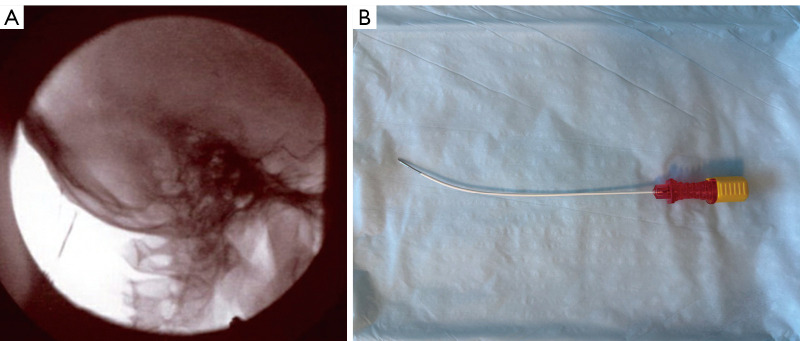

Background: This manuscript presents the challenges of treating various forms of headaches and the potential of interventional techniques targeting the greater occipital nerve (GON) to alleviate the burden on patients. Occipital neuralgia, characterized by stabbing or shooting pain in the base of the skull, is often associated with primary, cervicogenic, or migraine headaches. While occipital nerve blocks offer temporary relief, durable treatment options are limited. Pulsed radiofrequency (PRF) and thermal radiofrequency ablation (TRFA) have shown promise as minimally invasive procedures for long-term treatment. However, GON is not easily identified using ultrasound or fluoroscopic analysis; thereby, minimizing success of proper ablation. Here, the authors provide a percutaneous strategy to localize the GON and maximize lesion performance. We intend to provide an ex-vivo description of staggered bipolar radiofrequency (RF) lesioning and include the use of staggered bipolar lesioning of the GON and stimulation of the semispinalis capitis. We also analyzed the effectiveness and side effects from this ablation, retrospectively.

Methods: Patients with chronic refractory GON neuralgia were selected for GON TRFA. A novel double needle technique of sequential electrical stimulation was used to localize the GON and approximate needle to nerve distance. Once the needles were positioned adjacent to the GON, TRFA was performed using a bipolar staggered technique.

Results: Twenty-two patients with GON were treated with TRFA using a novel double needle technique. Seventy-two percent of these patients reported greater than 50% pain relief at both 1 and 6 months following the procedure. The results of our ex-vivo study demonstrate that performing TRFA using the parallel needle bipolar approach separated 8 mm apart produced the most desirable lesion dimensions that may correlate with effective ablation of the GON.